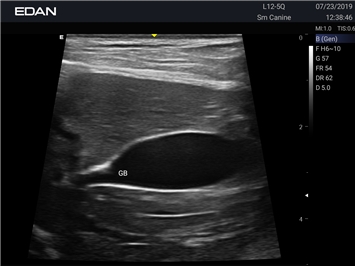

EDAN Acclarix AX2 VET

Ветеринарный ультразвук одним нажатием. Система Acclarix AX2 VET разработана с целью обеспечить бескомпромиссную производительность по доступной цене. Наличие уникальных двойных аккумуляторов в легком корпусе массой 4,5 кг из магниевого сплава позволяет системе Acclarix AX2 VET удовлетворять все потребности ветеринарных исследований, сохранив низкую стоимость.

EDAN Acclarix AX2 VET представляет собой специализированную ветеринарную ультразвуковую систему, сочетающую высокую производительность с доступной ценой. Благодаря продуманной конструкции и передовым технологиям, система обеспечивает качественную диагностику животных различных видов.